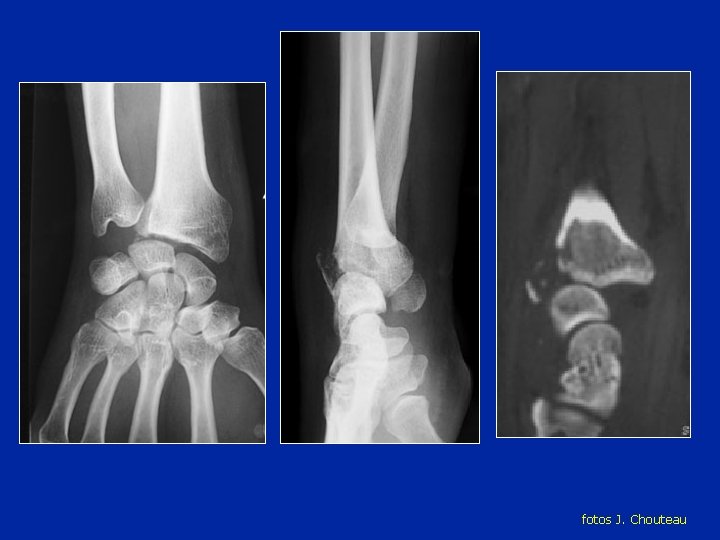

Luxación retrolunar del carpo

fotos J. Chouteau